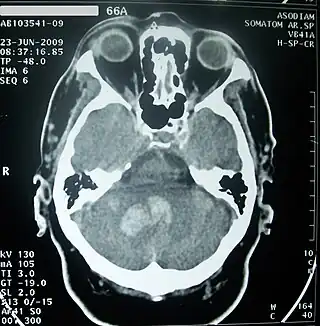

![]() TAC de cráneo mostrando hemorragia intracerebral profunda por sangrado en el cerebelo (zona grisácea), aproximadamente 30 horas desde su inicio. | ||